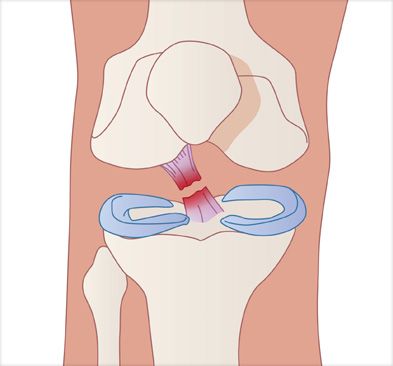

십자인대 완전 파열, 빠른 치료가 중요합니다.

수술을 하지 않고 방치하면 반월상 연골판 파열이나 관절 연골 손상 등으로 이어져 퇴행성 관절염 위험이 높아집니다.

십자인대 재건술은 손상된 인대를 자가건이나 타가건을 활용해 원래의 인대의 위치에 재건하여 무릎의 기능을 회복시킵니다.